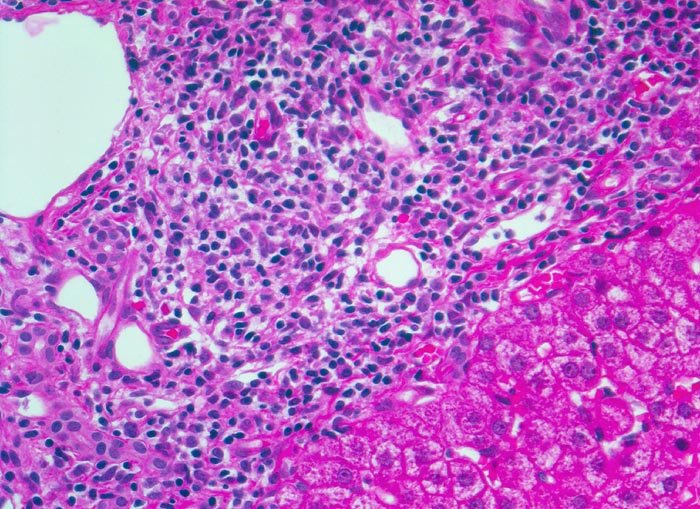

Morphologische Merkmale:

• Dichte mononukleäre portale und lobuläre Entzündungsinfiltrate mit Ausbildung von Lymphfollikeln in den Portalfeldern.

• Übergreifen der Entzündung auf das Parenchym (=Interface oder Grenzzonenhepatitis).

• Abgerundete hypereosinophile apoptotische Hepatozyten (Councilman-Körperchen).

• Geringe Portalfeldfibrose. Das sollte der Kliniker dem Pathologen mitteilen: